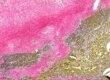

犬口腔T細胞淋巴瘤 (T cell lymphoma)

以anti-CD3及anti-CD20抗體進行免疫組織化學染色(immunohistochemistry, IHC),鑑別犬隻口腔的圓形細胞瘤(round cell tumor)。可看到腫瘤細胞呈現強CD3細胞膜陽性訊號(membranous signals),且CD20呈現陰性表現。IHC結果顯示腫瘤細胞為T細胞來源。

染色套組:TAHC03D